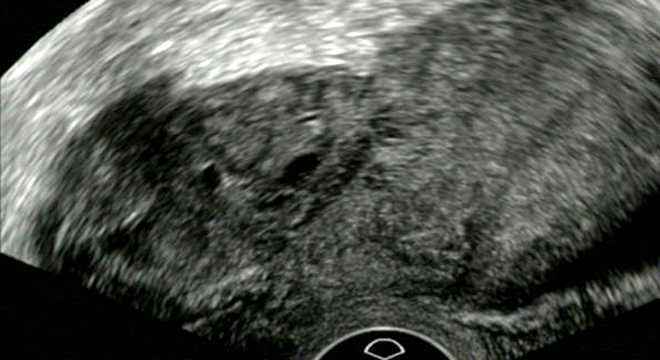

Blasensteine: Röntgenbild

Zur Diagnose von Blasensteinen werden verschiedene Untersuchungen und Abklärungen durchgeführt. Dazu gehören unter anderem:

• Röntgenaufnahmen der Blase